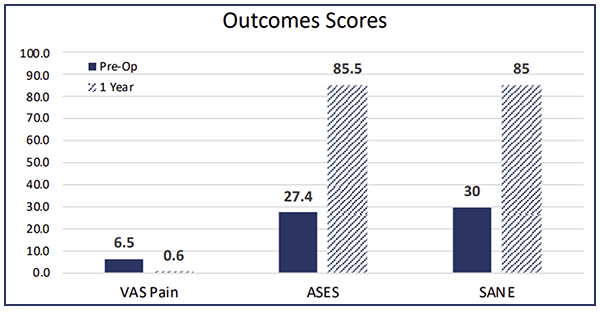

This is a patient that’s been in pain for quite some time and was clinically improving. You can see the outcome scores show dramatic improvement.

We're up to 26 months at this point. Our patients are enrolled in a registry, and you can see the follow-up. What's really fascinating, is I am not typically using BioBrace® for those little sweetheart, one centimeter supraspinatus tears. Every single one of these patients enrolled in this study has been someone that’s had a bad tear pattern. These are hard rotator cuff repairs where you worry whether they're actually going to heal or not. You can see here, 46 patients at this point, with 26 primaries, and 23 of those are still viable and intact.

If you look at the literature for these types of tear patterns, failure rates are as high as 35–40%. These are not repairs you're typically very confident about…so these types of numbers, although early, are still very impressive.

And these repairs typically fail early. They could be failing on the way to the PACU! So when they start lasting two, three, four months and your patients are doing clinically well with functional range of motion, you should be pretty excited.

In the revision situation, which is even worse as far as the numbers are concerned, 17 patients have had revision rotator cuff repairs with BioBrace® and only two have gone on to retear. Again, pretty remarkable.